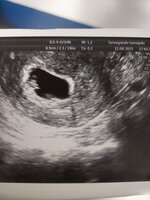

Ihanaa! Paljon onneaUltrakuulumisia pyydettiin, joten laitetaan tulemaan :)

Sykkeellinen sikiö löytyi ja viikot vastaa 6+3 niin kuin olin ajatellutkin olevan![]()